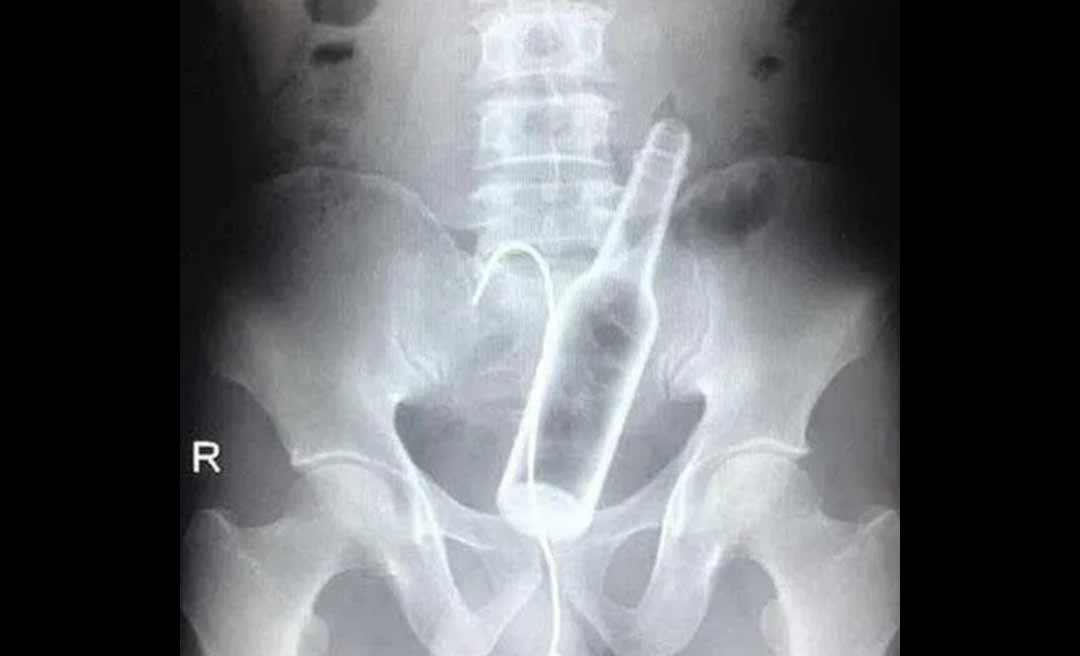

Um jovem de 25 anos, que não teve seu nome revelado, foi transferido no sábado (8) do Hospital Raimundo Chaar, em Brasiléia, no interior do Acre, para o Pronto-socorro de Rio Branco, com uma garrafa de vidro no ânus, segundo o jornal O Alto Acre, informativo eletrônico da fronteira.

Após uma rodada de cerveja, já bêbado, o homem resolveu desafiar o perigo ao "brincar", segundo testemunhas, de introduzir a garrafa no ânus, mas acabou se dando mal.

Desesperado, o rapaz acionou o Samu. Os socorristas o conduziram ao Hospital Raimundo Chaar, porém os profissionais não conseguiram retirar a garrafa e resolveram transferi-lo para a capital onde o jovem foi submetido a uma cirurgia para remoção do objeto.